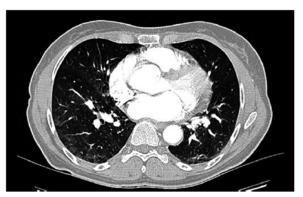

肺动脉CT血管造影技术(CTPA):未见肺栓塞征象,双肺轻度磨玻璃影,感染或肺水肿可能(图2)。